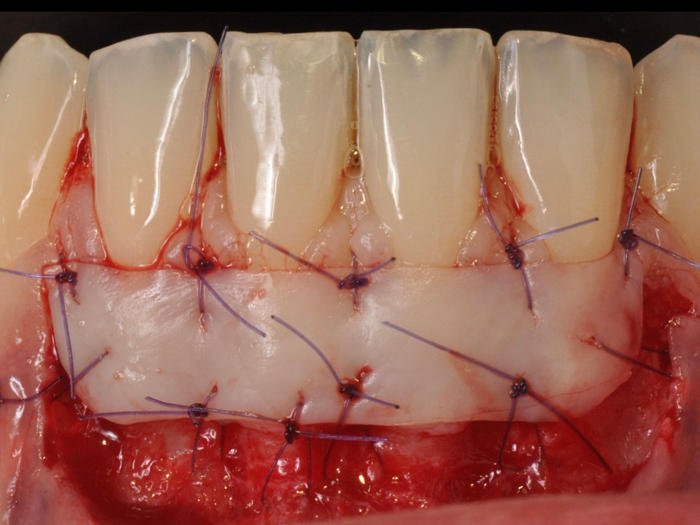

Greffe de conjonctif selon la technique de Langer, (de gauche à droite) : tracé

d'incision du lambeau muco-gingival, adaptation du greffon conjonctif sur le site

receveur, suture du lambeau repositionné in situ.

d’incision du lambeau muco-gingival, adaptation du greffon conjonctif sur le site

Greffe de conjonctif associée à un LPC (de gauche à droite) : Incisions,

suture du greffon, traction coronaire du lambeau